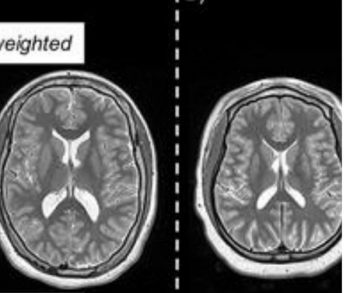

New research suggests that an emerging predictive biomarker, derived from a combination of magnetic resonance imaging (MRI) brain scans and a machine learning algorithm, has significantly greater accuracy than previously established measurements for diagnosing Alzheimer’s disease.